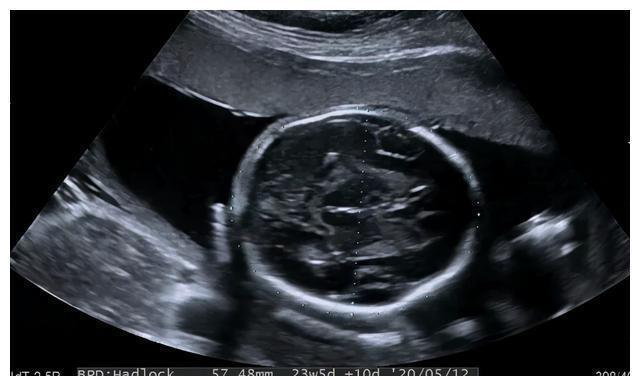

美国妇产科协会强调,不管使用哪种方法,亦不管妊娠在那一阶段,即使让最有名的专家进行彻底的检查,期望能将所有胎儿畸形均能被检测出来是不现实,也是不合理的。卫生部《产前诊断技术管理条例》规定于妊娠18~24周应诊断的致死性畸形包括无脑儿、严重的脑膨出、严重的开放性脊柱裂、严重胸腹壁缺损内脏外翻、单腔心、致死性软骨发育不全。顺义妇儿医院在孕20-24周进行产筛检查,该阶段胎儿多个器官已发育成熟,羊水量适中,胎儿相对容易变换体位,有利于超声筛查胎儿结构。根据中国医师协会超声医师分会颁布的《中国产科超声检查指南》,产筛超声检查内容如下:

(1)胎儿头颅:观察颅骨强回声环,观察颅内重要结构,包括大脑半球、脑中线、侧脑室、丘脑、小脑半球、小脑蚓部、颅后窝池;